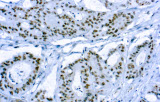

- Linfoma a cellule mantellari: ciclina D1 e SOX11 come marcatori chiave, incluso supporto per i casi ciclina D1 negativi.